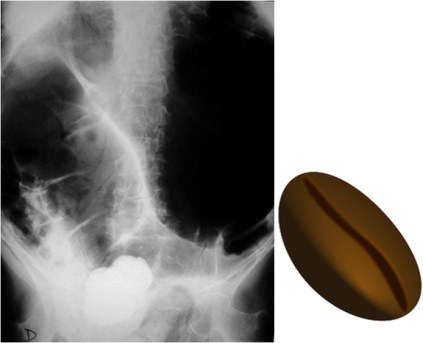

SIGNO DEL GRANO DE CAFÉ

Signo de obstrucción intestinal con estrangulación (vólvulo, hernia incarcerada,…), que provoca obstrucción simultánea a dos niveles -asa cerrada-. El asa afecta, llena de aire y doblada sobre sí misma, adquiere el aspecto de un grano de café con una banda central densa que corresponde a las paredes opuestas del asa estrangulada. Cuando la radiografía es en bipedestación puede aparecer un nivel hidroaéreo en cada segmento del intestino dilatado.

La fotografía corresponde a un paciente con vólvulo de sigma. Suele ser habitual en pacientes con vólvulo de sigma que el grano de café ocupe casi todo el abdomen. Hasta un 80 % de estos vólvulos se diagnostican solo con la radiografía de abdomen en decúbito. La ausencia de gas rectal contribuye a reforzar el diagnóstico.

El signo también ha sido descrito en obstrucciones en asa cerrada de intestino delgado, pero lo más habitual es que se aplique al vólvulo de sigma.

El Signo del grano de café también se ha llamado Signo de la U invertida y Signo del tubo doblado

Referencia. Feldman D. The coffe bean sign. Radiology 2000; 216: 178-179. En: